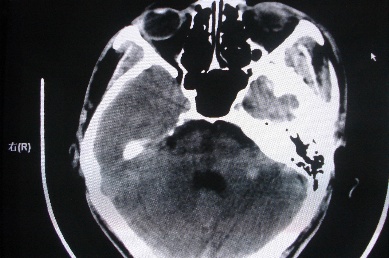

以下是引用zhangzhongshou在2007-4-18 17:49:00的发言:[br]脑实质内多发高密度结节影,支持肉芽肿得诊断,究竟是结核性、真菌性或寄生虫性的需结合临床,进一步检查确诊,但从影像上无法鉴别,只是临床上结核性肉芽肿最为多见而已。